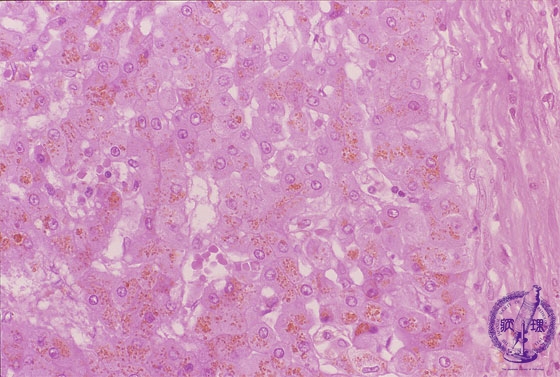

Microscopic image (HE stain, high power): Most of the hepatocytes within regenerative nodules contain coarse golden brown granular deposits (hemosiderin).